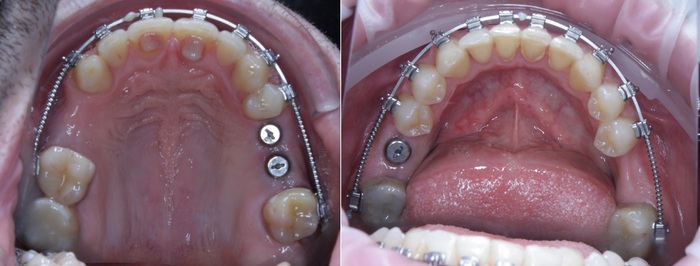

Произведена установка 3 имплантатов и синус-лифтинг в области 5-го и 6-го зуба на верхней челюсти и 6-го на нижней. В полости рта это выглядело примерно так:

Спустя примерно 3 месяца пришла очередь левой стороны:

Также были установлены 2 имплантата и проведен синус-лифтинг на верхней челюсти (в области 5-го и 6-го зуба) и 1 на нижней (в области 6-го зуба).

В полости рта это выглядит так:

Я решил добавить фотографии сразу после снятия брекетов, а не с ними, как это было на рентгеновском снимке. Думаю, так выглядит намного симпатичнее.

Коронки страшненькие – на то они и временные. Такой тип коронок необходим для «доформирования контура десны» и для того, чтобы «ввести области в жевание» из-за длительного отсутствия зубов. Необходимо подготовить мышцы, связки, сустав, остальные зубы к нормальному жеванию. Временные коронки можно корректировать при необходимости.

Шло время. Так же молниеносно, как проходит молодость. Ещё 3 месяца и пора менять временные коронки на постоянные. Кстати, средний срок использования временных конструкций как раз 3-4 месяца. Почему? Как минимум, пластик истирается, как максимум, очень хорошо задерживает на себе еду и зубной налёт, что при хреновом уходе приводит к воспалению и проблемам.

В процессе лечения 7-ой зуб на нижней челюсти треснул, появился скол, пришлось от него тоже избавиться. Ниже снимок с постоянными коронками и «внеплановым» имлпантатом:

Коронки на этом снимке уже четко различимы, потому что сделаны из керамики.

Вид «изнутри»:

Полость рта всё больше начинает преображаться.

Ещё один квантовый скачок и проходит 3.5 месяца. Выход на сцену временной коронки на имплантате, который был установлен позже остальных:

Вы её видите? И я не вижу. А она есть: